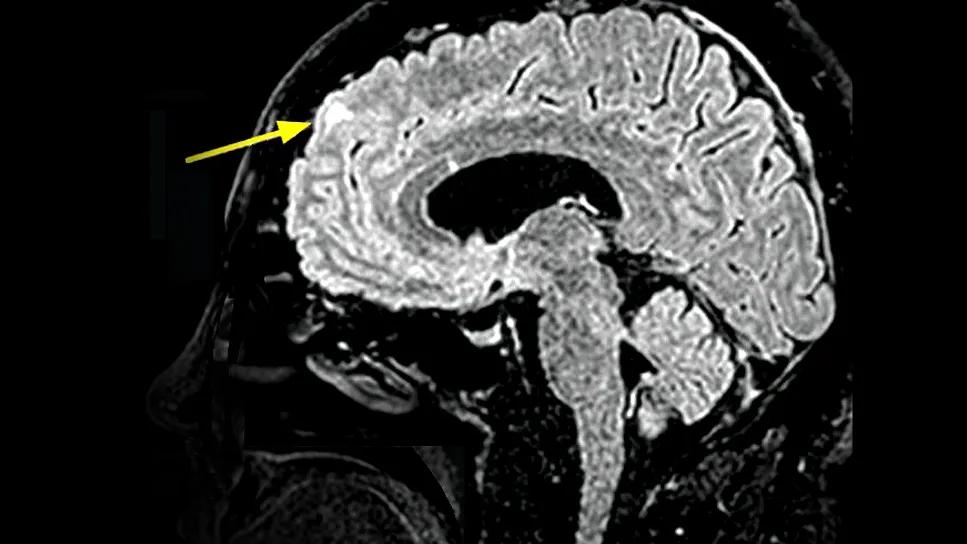

brain MRI with arrow pointing to a cortical tuber

• Neuropsychiatric TSC (Cluster 3): In this group (17.6%), neurodevelopmental disorders predominated (e.g., autism, intellectual disabilities, neuropsychiatric conditions) and were accompanied by a high frequency of focal seizures, cortical tubers (example indicated by the arrow in the MRI at the top of this article) and subependymal nodules.